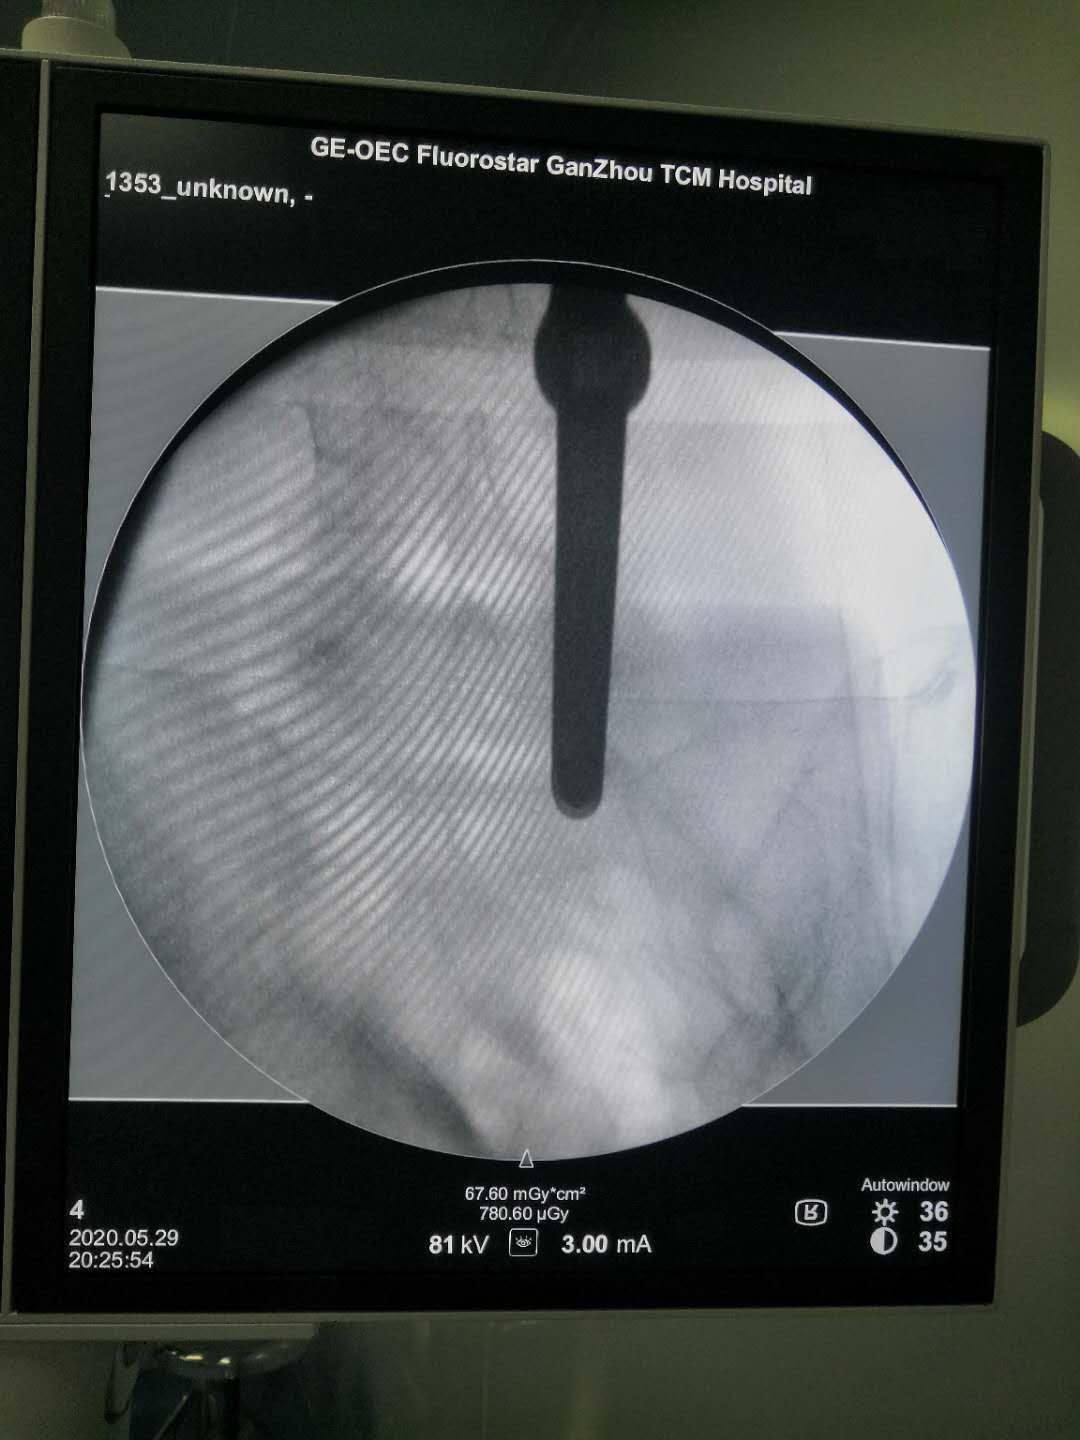

患者来我科治疗前,已经行走困难,行走大约500米就疼痛难忍,必须停下来休息。通过综合考虑,患者老年,同时有高血压病,冠心病等心血管病史!我们建议行微创手术治疗!

经过1小时的努力,胜利完成了手术!老奶奶的腰痛得到缓解!进行直腿抬高试验70阴性,加强试验阴性!